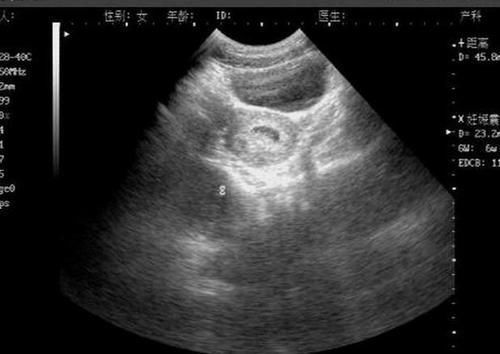

文章插图